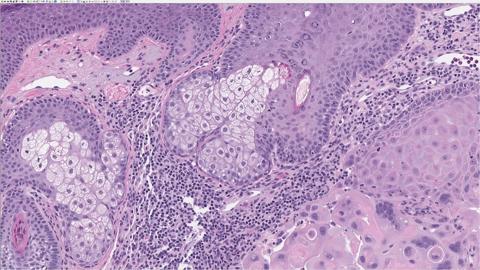

我们的数字病理学解决方案

数字病理学的趋势

数字病理学的最新进展